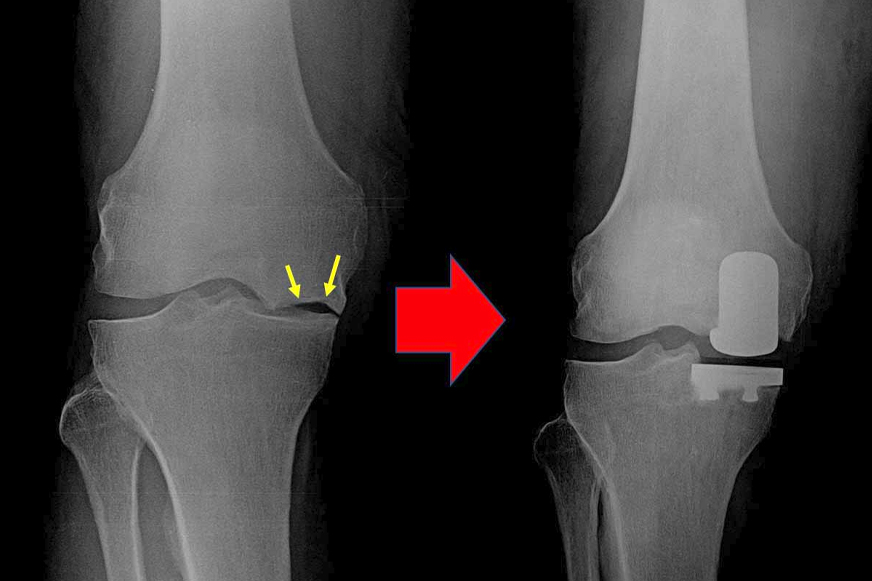

Your doctor may recommend knee replacement surgery to you after other non-surgical methods fail to provide relief. But not all such issues necessitate complete knee joint replacement. If damage is not widespread and limited only to one component of the knee joint, then healthy joint components are preserved with the partial knee replacement surgery.

Partial knee replacement (PKR) is also called unicompartmental knee replacement because in this surgical procedure only the damaged portion of the knee joint is replaced with an artificial implant.

The surgery is usually completed between one and two hours. The damaged bone and cartilage are taken out during the procedure, and bone cement or press-fit techniques are used to fix the implants. Before closing, the alignment and stability of the joint are checked.